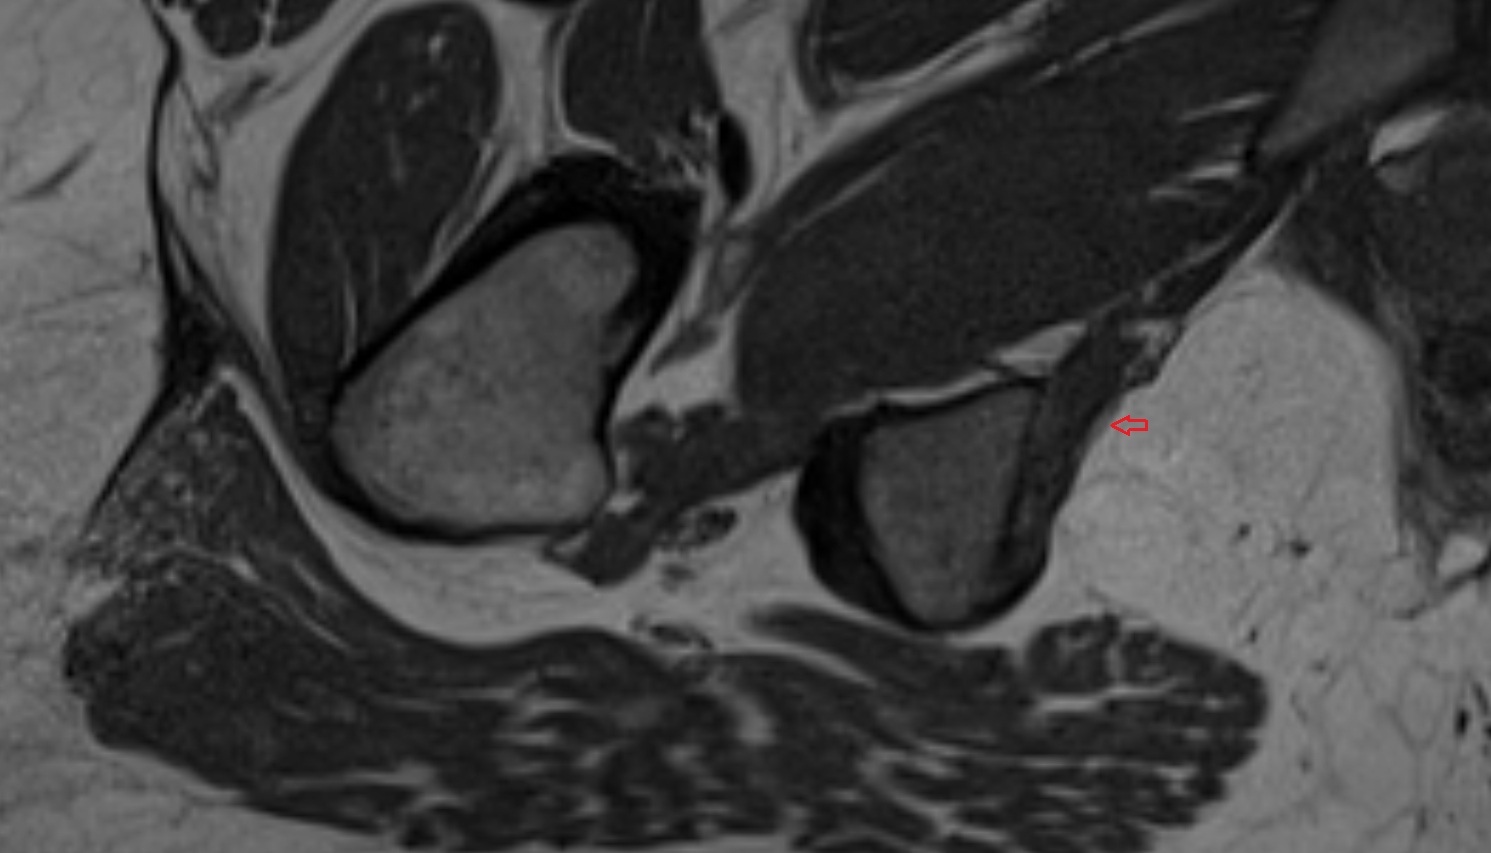

- Hip joint

- Head of femur

- Neck of femur

- Acetabular labrum

- Articular capsule of hip joint

- Acetabulum

- Ligamentum teres (ligament of the head of femur)

- Iliofemoral Ligament superior band (transverse band, lateral band)

- Iliofemoral Ligament inferior band (vertical band, medial band)